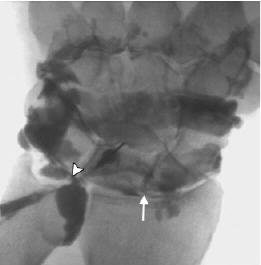

![]() |

| A 19-year-old woman with noncommunicating tear of triangular fibrocartilage at ulnar insertion in right wrist due to fall off skateboard five months before examination. Arthroscopy showed communicating tear of triangular fibrocartilage at this location. Coronal T1-weighted image obtained with fat-saturated spin-echo sequence (TR/TE, 525/15) shows noncommunicating defect (arrow) in ulnar attachment of triangular fibrocartilage. |

| Same patient as above. Conventional arthrogram of distal radioulnar joint shows contrast agent pooling in triangular fibrocartilage defect (arrowheads). Rüegger C, Schmid MR, Pfirrmann CWA, Nagy L, Gilula LA, and Zanetti M. "Peripheral Tear of the Triangular Fibrocartilage: Depiction with MR Arthrography of the Distal Radioulnar Joint" (AJR 2007; 188:187-192). |